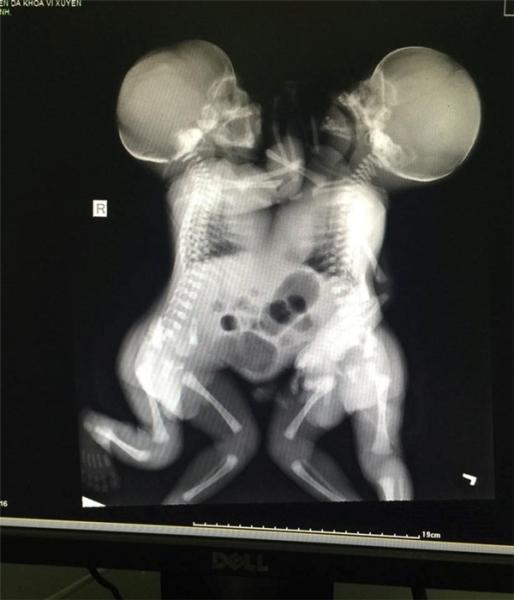

Đến khi bắt tay vào mổ lấy đứa bé, cả ê-kíp mới giật mình khi thấy 2 đứa trẻ dính liền nhau từ ngực, đến bụng, và có chung một dây rốn. Theo lời của bác sĩ Nguyễn Ngọc Chung (Phó Giám đốc Bệnh viện Vị Xuyên), khi đứa bé thứ hai được đưa ra khỏi bụng mẹ thì đầu đã tím đen, cả ê-kíp phải nhanh chóng cấp cứu cho cả hai đứa trẻ. Thật may mắn vì sau đó tình trạng của hai bé đã ổn định lại và được chuyển vào phòng chăm sóc đặc biệt tại khoa Nhi của bệnh viện. Được biết, tổng trọng lượng của cả hai đứa trẻ khi vừa sinh ra là 4,9kg.

Sau các đợt kiểm tra sơ bộ cho hai bé con của chị Chẩy thì các bộ phận tim, phổi, thận vẫn tách rời. Tuy nhiên, bệnh viện vẫn tổ chức cuộc hội chẩn lớn, bao gồm cả ban lãnh đạo, và nhất trí phải chuyển hai bé xuống Hà Nội để kiểm tra kĩ hơn vì sức khỏe không mấy khả quan.